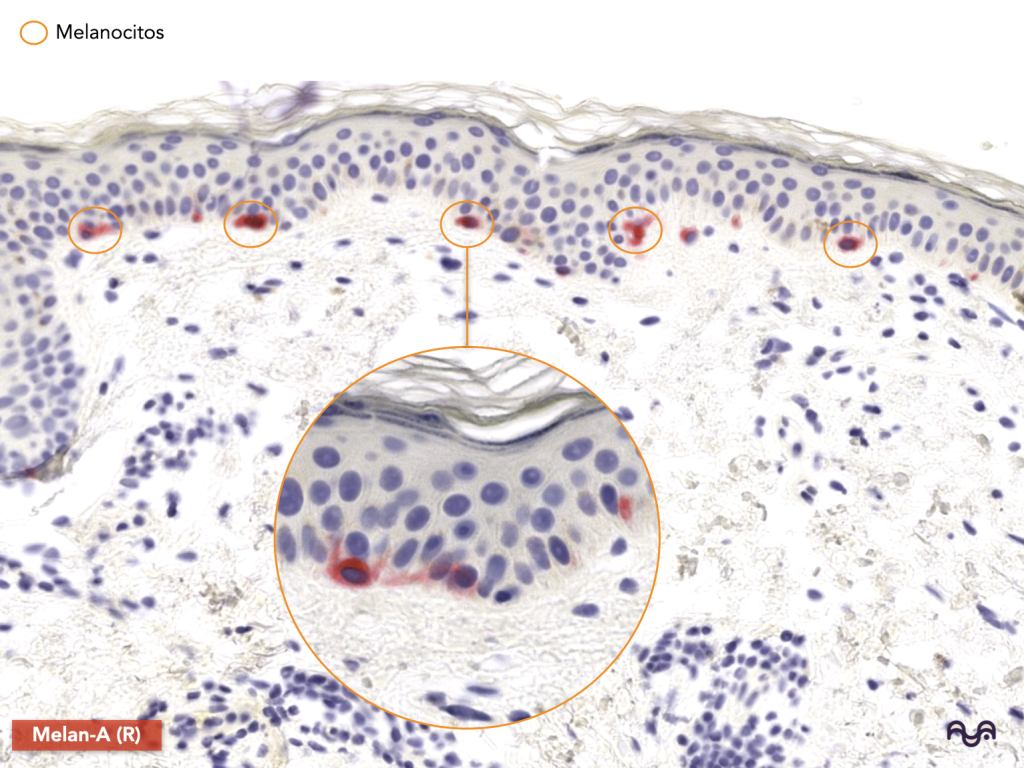

Los melanocitos derivan de la cresta neural, residen esencialmente en la capa basal y transfieren melanosomas («paquetes de melanina») a los queratinocitos. Mort 2015

Melanocitos

Origen: cresta neural.

Función: producción de melanina y transferencia de melanosomas (fotoprotección). Mort 2015

Cómo verlos en H&E: a menudo son discretos; sugiérelos por ubicación (basal) más que por “verlos” claramente. En docencia, se entienden mejor con tinciones/inmuno (ver foto con tinción para Melan-A).

Melanocitos/Langerhans/Merkel: lo clave en este módulo es ubicación y función, no “forzar” su identificación en H&E de rutina (porque suelen requerir de tinciones especiales para su visualización). Mort 2015; Romani 2010; Woo 2015